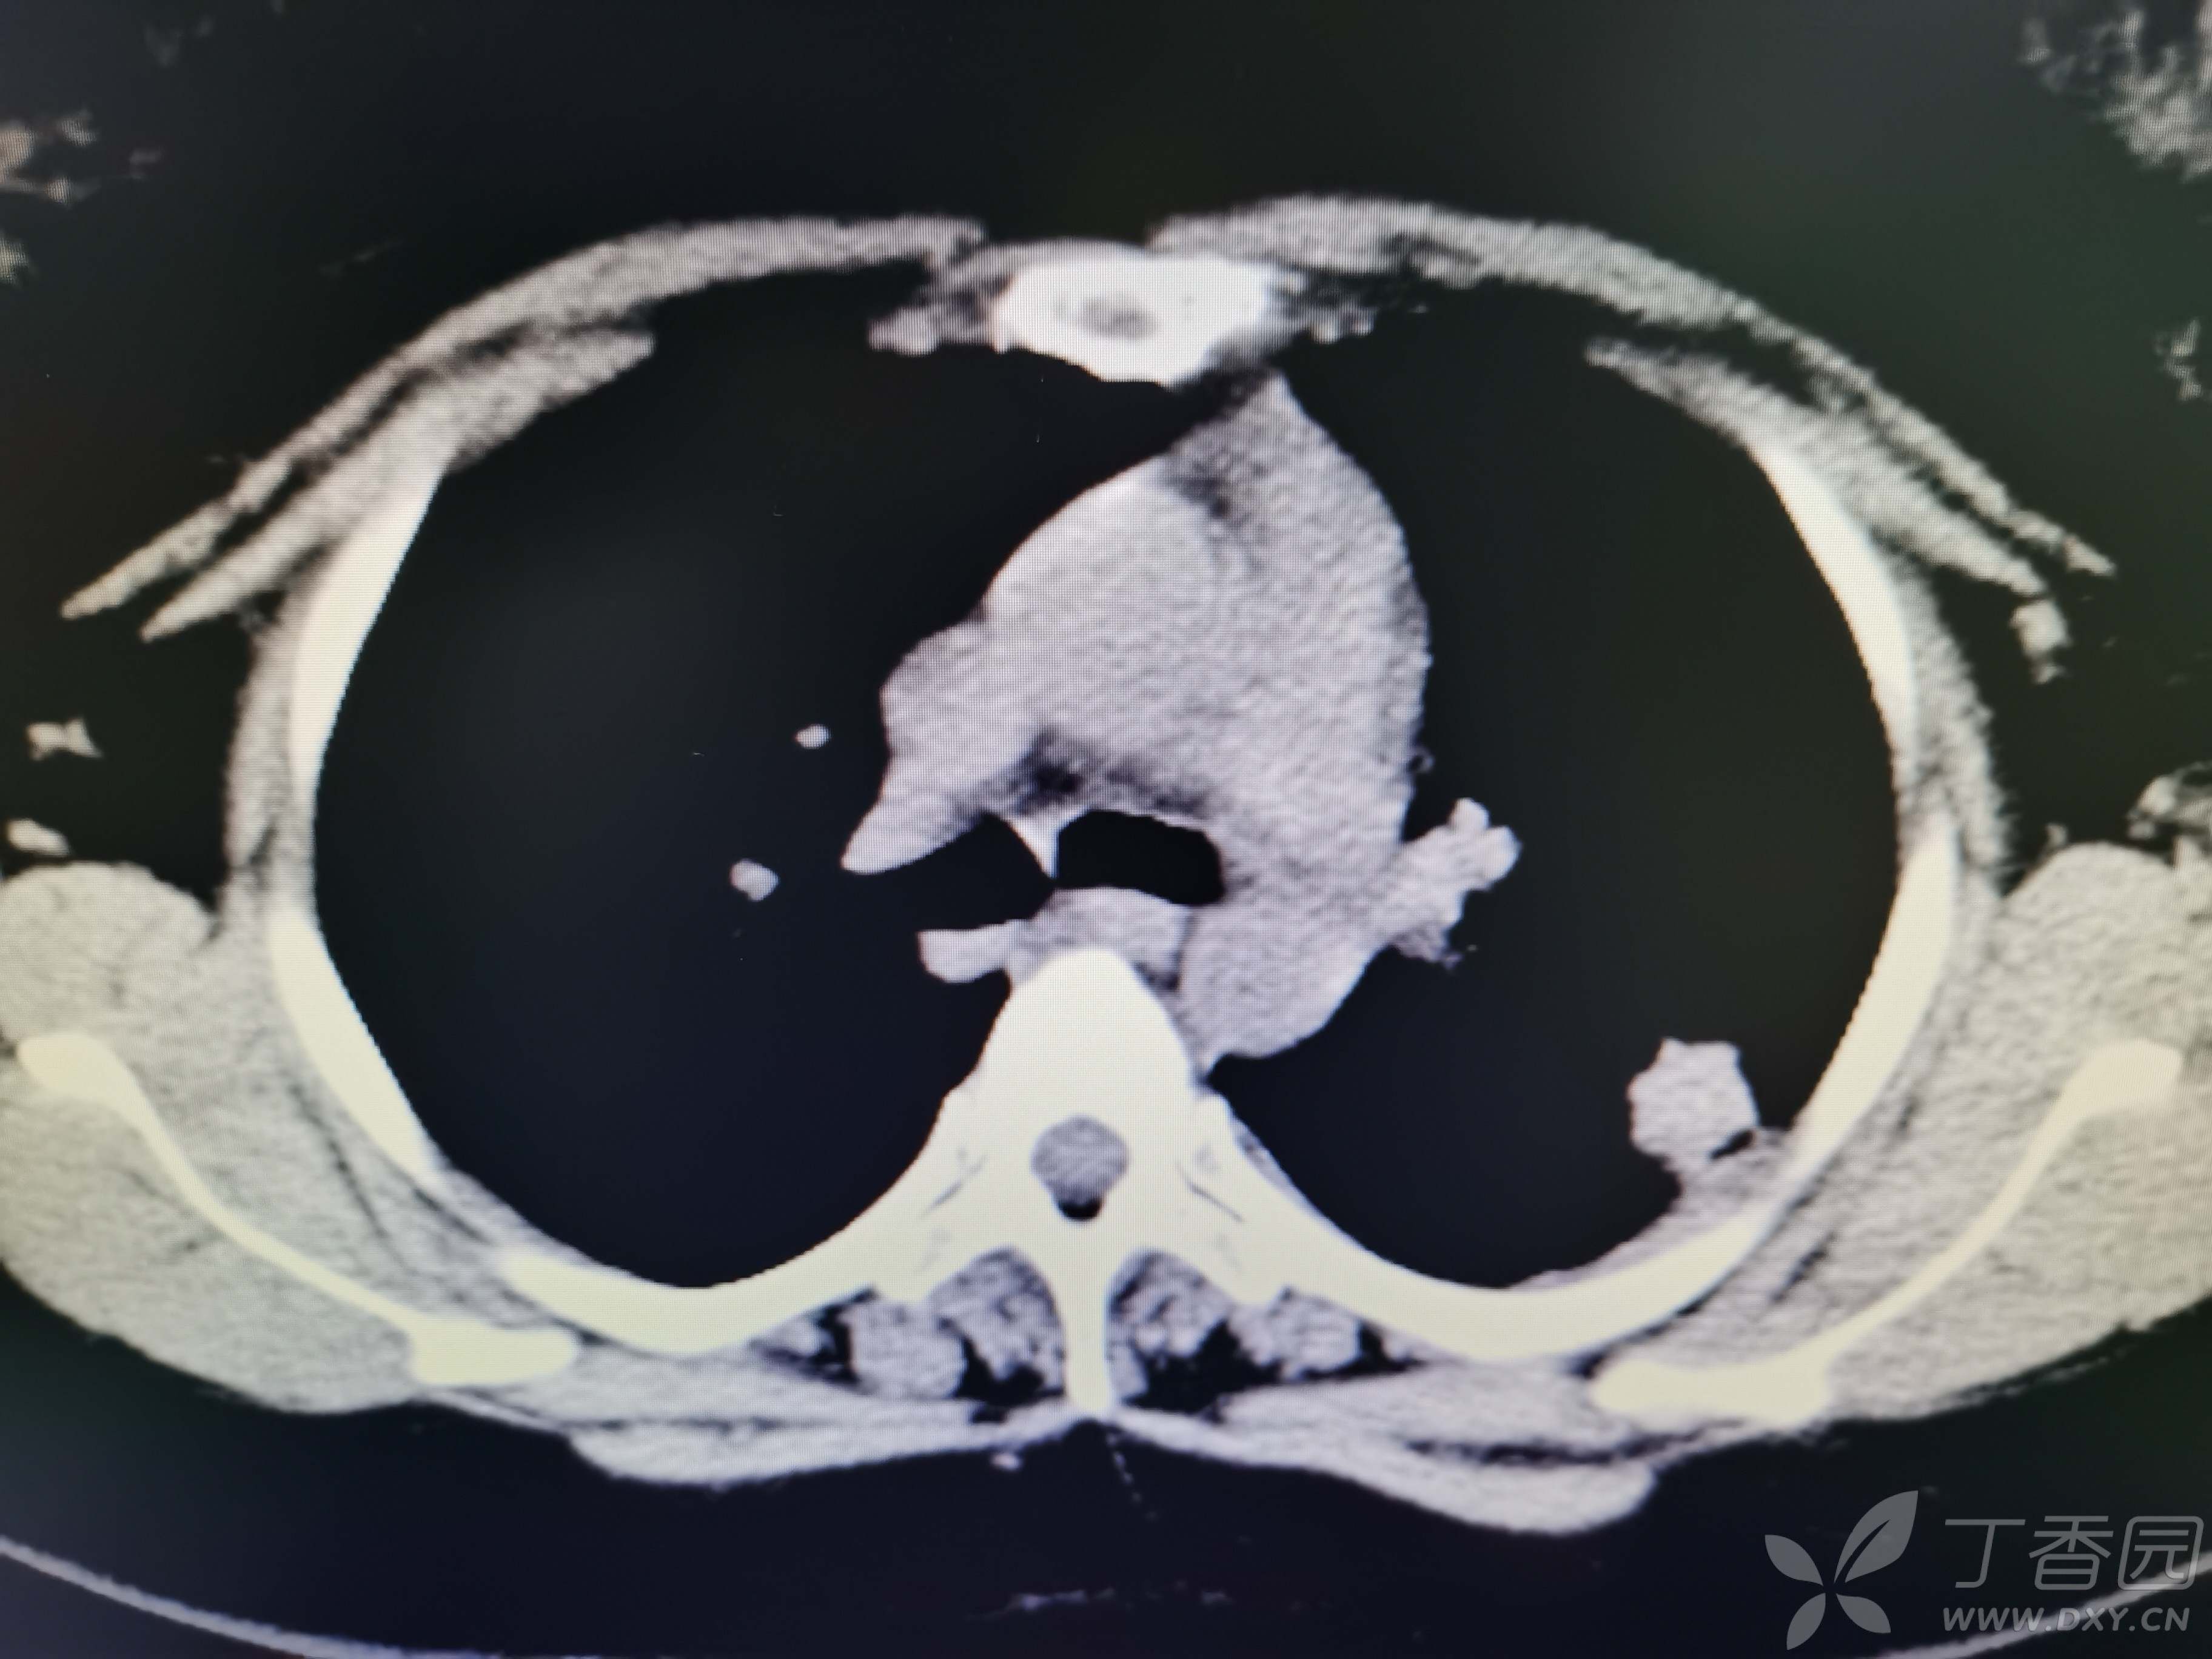

基本信息:女,三十几岁,印度人。。

胸部CT:

如题:猜肺部病灶病理。。